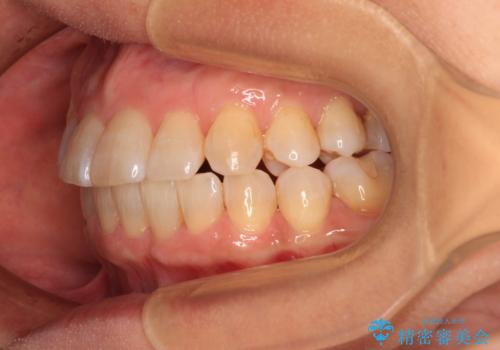

- 骨格的な咬み合わせのズレ、前歯のデコボコとクロスバイトを気にして来院された患者様です。

奥歯の噛みにくさが顕著なためマウスピースではなく、ワイヤー装置による矯正治療を行うこととしました。

下顎の正中を歯1本分ずらした位置とすることで、外見上の骨格的なずれをカバーするように計画しました。

クロスバイトを改善したことで、前歯の負担が軽減し、安定して噛めるようになりました。